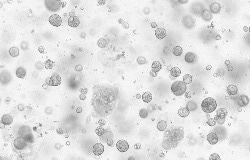

Human breast cancer organoids

Human breast cancer organoids were cultured with FGF7 (Cat#: 10210-H07E), RSPO1 (Cat#: 11083-HNAS), IGF1 (Cat#: 10598-HNAE), EGF (Cat#: 50482-MNCH), NRG1 Beta 1 (Cat#: 11609-H01H), and NOG (Cat#: 50688-M02H). Image Credit: Sino Biological US Inc.